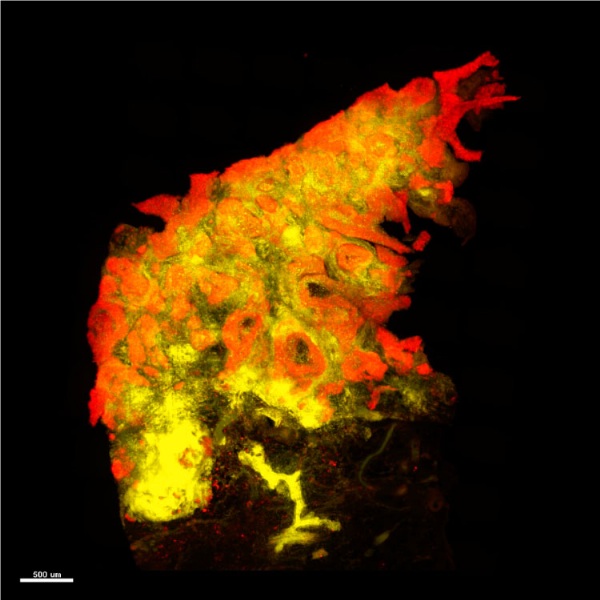

諾倫科技結合專利技術與自有研發團隊,創立3D病理影像技術平台,且為提供高品質、高穩定的3D病理影像,推出一站式的3D全組織病理影像服務。

目前可將厚達1.5cm的小鼠腦與各式鼠類器官進行3D影像掃瞄成像,也能執行2mm的腫瘤組織。

諾倫科技結合專利技術與自有研發團隊,創立3D病理影像技術平台,且為提供高品質、高穩定的3D病理影像,推出一站式的3D全組織病理影像服務。

目前可將厚達1.5cm的小鼠腦與各式鼠類器官進行3D影像掃瞄成像,也能執行2mm的腫瘤組織。